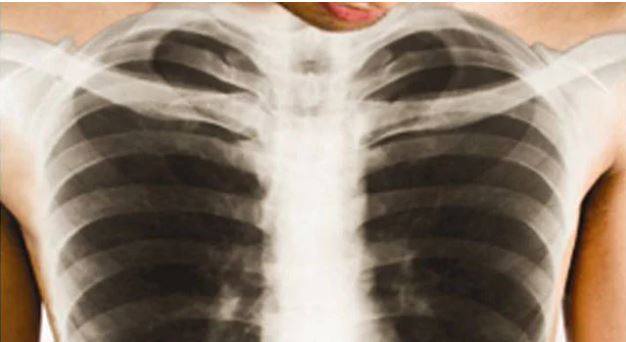

Imibare ya Minisante igaragaza ko Abarwaye igituntu biyongereyeho hafi 4,000 mu mwaka umwe

Imibare ya Minisiteri y’Ubuzima (MINISANTE), igaragaza ko abarwaye Igituntu biyongereyeho hafi 4,000 mu gihe cy’umwaka

Ibi ngo bishingirwa ku kuba baravuye ku 5,538 bariho muri 2021/2022, bagera 9,417 muri 2022/2023, bivuze ko biyongereyeho 3879, naho mu mwaka wawubanjirije wa 2020/2021 bari 5435.

Muri iyi mibare, abibasiwe cyane n’abatuye mu Ntara y’Iburasirazuba, kubera ko mu bantu 9417 bagaragayeho igituntu muri 2022/2023, abagera 3713 ari ab’Iburasirazuba, abagaragaweho n’iyo ndwara mu Mujyi wa Kigali bari 2239, mu Majyepfo hari hagaragaye 1682, Iburengerazuba bari 1114, mu gihe mu Majyaruguru ariho hagaragaye bacye kuko ari 669.

Muri uwo mwaka kandi byagaragaye ko abagabo ari bo bari bibasiwe cyane, kuko bakubye inshuro zirenga 3 abagore, kubera ko abagera ku 7345 bangana na 78% bari abagabo, mu gihe abagore bari 2072 bangana na 22%.

Imibare y’ishami ry’Umuryango w’Abibumbye ryita ku buzima iheruka muri 2021, igaragaza ko mu Rwanda abantu 56 ku baturage ibihumbi 100 barwaye igituntu.